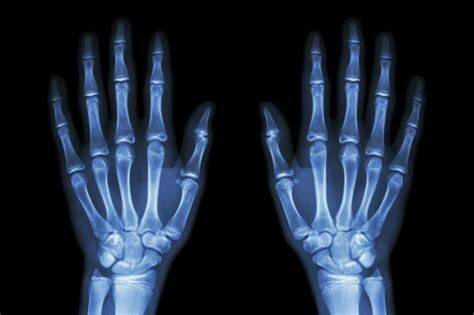

• Se hace la Primera Radiografía

Se hace la Primera Radiografía

Wilhelm Rontgen hizo la primera imagen de rayos X a la mano de una mujer, su esposa.